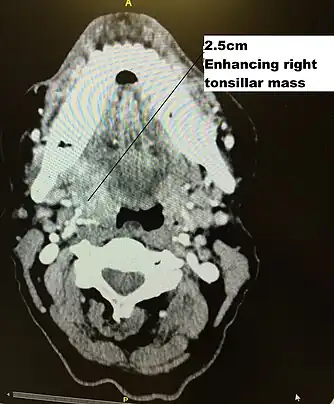

Diagram of radiation therapy contours used in treating a right tonsillar cancer

Transverse radiation contours used in treating cancer seen on above CT scan and in machine set up below